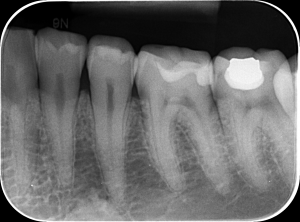

RADIOGRAFIA RETROALVEOLARA – cunoscută și sub numele de radiografie periapicală, este o radiografie dentară intraorală ce oferă o imagine detaliată a unui singur dinte sau a unui grup mic de dinți (maxim trei) și a țesuturilor din jurul lor, inclusiv a rădăcinilor, osului și gingiilor. Aceasta este utilizată pentru a detecta carii, leziuni periapicale (zone de infecție la vârful rădăcinii), abcese, tratamente de canal incorecte și probleme ale osului sau gingiilor.

PRET: 40 Lei

RADIOGRAFIE BITEWING –  este un tip de radiografie dentară intraorală care arată coroanele dinților din ambele arcade, permițând medicului dentist să depisteze cariile interdentare incipiente si sa intervina la timp astfel fiind cel mai bun instrument in preventia cariei dentare.